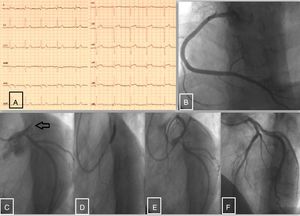

A) Electrocardiograma en urgencias. B) Arteria coronaria derecha sin lesiones angiográficas significativas. C) Oclusión trombótica proximal de la arteria descendente anterior; circunfleja sin lesiones angiográficas. D) Angioplastia con stent farmacoactivo de la arteria descendente anterior. E y F) Resultado final postangioplastia con stent farmacoactivo.

Se presenta el caso de un varón de 22 años de edad sin antecedentes de interés que acudió al servicio de urgencias de nuestro centro por dolor torácico. El paciente negaba tajantemente consumo de drogas; sin embargo, destacaba la presencia de una reciente tromboembolia pulmonar bilateral masiva en el hermano a la edad de 30 años. El dolor era de perfil típico para angina: centrotorácico; opresivo; de reposo; irradiado a cuello; acompañado de cortejo vegetativo y de menos de 2 h de duración. A su llegada, y según protocolo habitual de urgencias, se realizó un ECG de 12 derivaciones (fig. 1A). A pesar de la edad del paciente y de la ausencia de consumo de tóxicos, fue diagnosticado de IAMCEST y se inició doble antiagregación con ácido acetilsalicílico (100mg) y prasugrel (60mg). De manera urgente se realizó una coronariografía, en la que se objetivó una oclusión trombótica a nivel de la arteria descendente anterior proximal (fig. 1C). El resto de las arterias coronarias eran lisas (sin enfermedad aterosclerótica; fig. 1B). Se procedió a revascularización percutánea con implante de un stent farmacoactivo sin complicaciones (fig. 1D), con un excelente resultado final (fig. 1 E y F). Durante la evolución posterior en planta de cardiología no hubo eventos de interés, por lo que fue dado de alta con indicación de estudio por hematología para descartar algún tipo de status de hipercoagulabilidad.